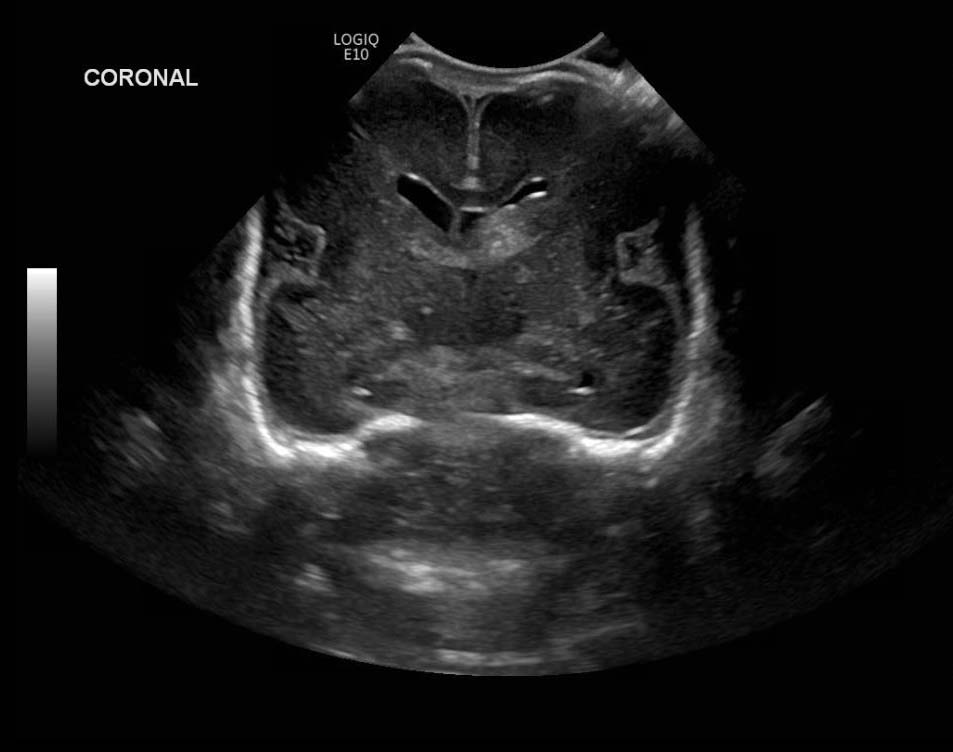

Age: 4 days (born at 24 weeks)

Sex: Male

Indication: Evaluate for germinal matrix hemorrhage

Grade 2 germinal matrix hemorrhage

Sample ReportLeft germinal matrix hemorrhage involving the caudothalamic groove and layering in the occipital horn of the left lateral ventricle without hydrocephalus (grade 2).

No abnormal brain parenchymal echogenicity or extra-axial collections.

Premature sulcation pattern.